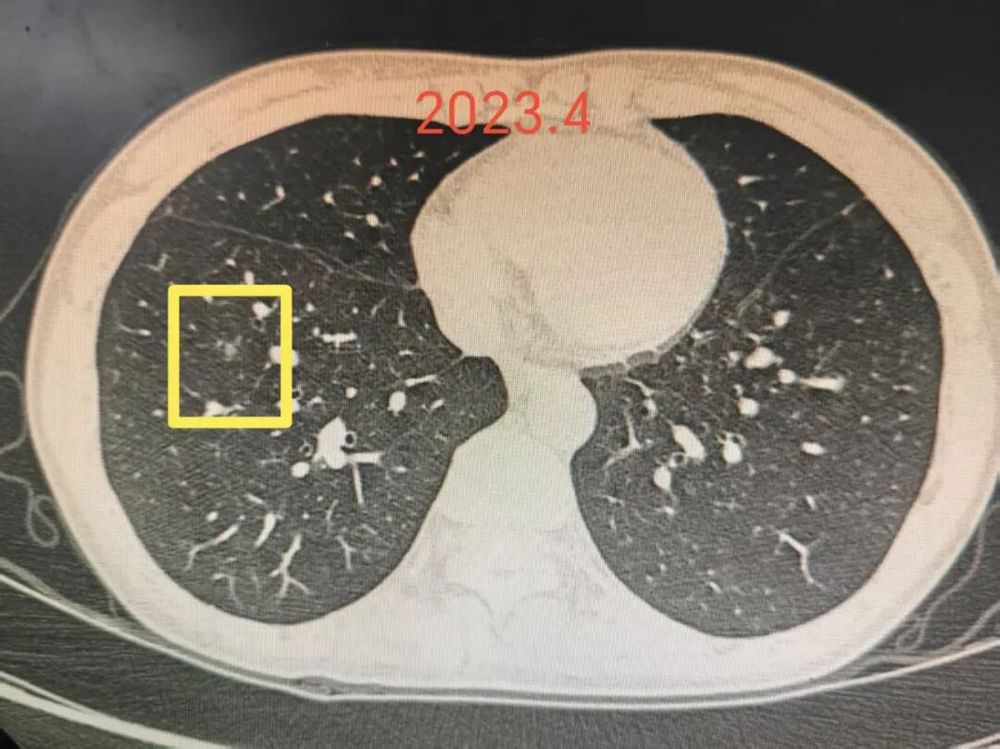

前言:肺多发结节考虑是多原发早期肺癌时,指南的意见是怎样的呢?

指南上说优先处理主病灶,兼顾次病灶,在不影响生存及符合无瘤原则前提下尽量切除病灶并尽可能保留肺功能。次病灶若是纯GGO,受限于心肺功能无法全部切除时,建议6-12个月随访1次。也就是说:如果心肺功能吃得消,即便次病灶是纯GGO,也是应该尽量切除。这个原则也是宣扬“一网打尽”处理肺结节的医生的指导性原则。但我总觉得指南也是人定的、脱胎于临床研究与回顾分析得出的结论肯定会落后于疾病的发展与时代的变化、疾病谱的改变,从而不一定适应临床。死守指南会导致患者肺功能受损明显、创伤太大、费用过高,而且无法解决导致多发病灶的机体内环境与外环境因素,从而难以避免后续随访中再检出新的病灶。所以我一直宣扬“抓大放小”。今天分享的这个病例右侧较为明显的有四处病灶,主病灶A在右下叶靠近叶间裂,次病灶一处在右上叶病灶B,一处在右下病灶C,还有一处密度很淡的病灶D是邻近病灶B的。我们是如何决策与考虑的?